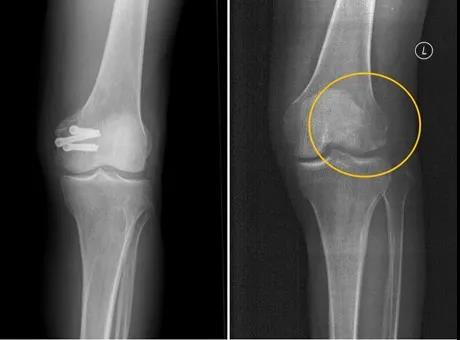

今年5月份,患者張強(化名),不慎扭傷,造成左股骨遠端骨折。由于骨折部位靠近關節(jié)面,使用金屬螺釘固定時應力過大,會影響骨折愈合;一年后還需要手術再次取出,造成二次創(chuàng)傷?;颊呷朐褐螅瑘F隊經(jīng)過詳細探討病情、細致閱片后決定,該患者符合蠶絲螺釘固定的適應證。術中使用蠶絲螺釘對骨折塊進行牢靠固定,術后的CT片中沒有任何偽影,可以清晰地看到骨折塊已經(jīng)完全復位,解除了患者二次手術取出的負擔和困擾。

術前(左)及術后(右)三維CT圖像